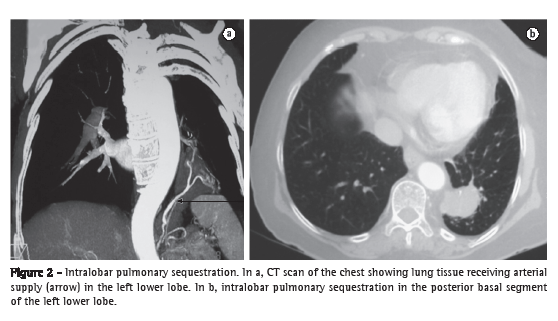

Both types of pulmonary sequestration receive their blood supply from the systemic circulation (Figure 2), generally via the descending thoracic aorta or the abdominal aorta.(4,11-13,18,19) In approximately 15% of cases, blood supply is provided by a different systemic artery.(11,13,18,19) In intralobar pulmonary sequestration, venous drainage is into the pulmonary veins,(18) whereas it is into the systemic venous system (azygos vein or portal vein) in extralobar pulmonary sequestration.(10,18,19)

In the prenatal period, it can be difficult to diagnose pulmonary sequestration by ultrasound, because extralobar sequestration can be mistaken for a normal lung (the tissues having similar characteristics), whereas intralobar sequestration can be incorrectly diagnosed as congenital cystic adenomatoid malformation (CCAM).(5) Nuclear magnetic resonance imaging can be useful in clarifying the diagnosis in such cases.(22) Extralobar pulmonary sequestration accounts for approximately 23% of the pulmonary lesions that are diagnosed in the prenatal period.(18) Of those, up to 68% can disappear over the course of the prenatal radiological follow-up period.(11) A CT scan of the chest reveals the sequestered lung tissue and its vascularization, as well as other associated malformations, if present.(11,15) The test of choice for the postnatal diagnosis is CT angiography.(11,13,15,18) Until recently, conventional angiography was the gold standard for demonstrating the arterial supply and venous drainage of such lesions. Currently, CT angiography is used instead of conventional radiography because the former is less invasive and more efficient in diagnosing such lesions, showing the vascularization of the sequestered tissue in great detail and therefore allowing safer surgical planning.(10-12,19,23)